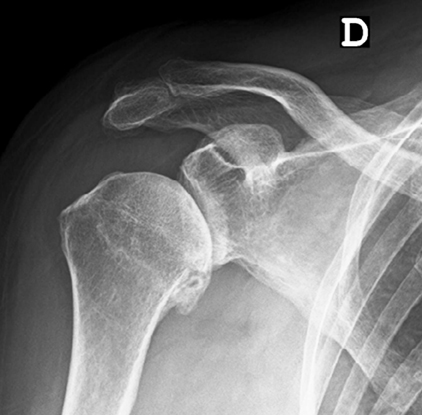

Normalmente o diagnóstico é feito através da radiografia (fig. 6) e tomografia computadorizada (para melhor determinar a versão da glenoide ou seu stock ósseo) (fig. 7) ou ressonância magnética (melhor avaliar integridade da coifa dos rotadores e infiltração gorda).